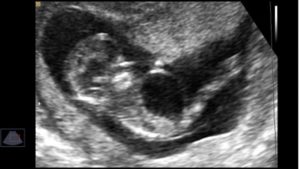

На ультразвуковом исследовании мочевик визуализируется в виде грушевидного или округлого образования. Орган имеет тонкие стенки, расположен в нижней области туловища и увеличивается в размерах в течение беременности матери.

Для определения его размеров необходимо принимать во внимание его наполненность. В случае отсутствия эхотени, рекомендовано проведение УЗИ по истечению 30−40 минутного периода. Врожденные и приобретенные патологии, пороки развития мочеполовой системы помогает обнаружить скрининговое УЗИ.

Атрезия уретры — называют редким заболеванием, обнаруживают на 14 — 15 неделе. На снимках выявляют мочевой пузырь значительных размеров у ребенка, что ведет к увеличению живота у плода, а у матери отсутствие околоплодных вод.

Мочевой пузырь плода определяется только на 12 или 13-ю неделю беременности. Размеры его будут различаться от степени его наполненности, а опорожнение его можно будет заметить по появляющемуся турбулентному потоку в области половых органов. Лучше всего это становится заметным при опорожнении мочевого пузыря плода мужского рода.